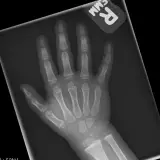

Peds Radiographs